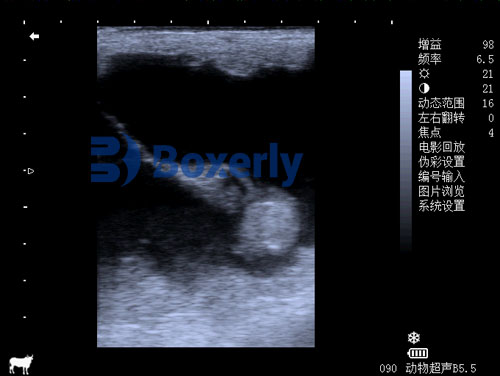

Mature follicles are usually 35–45 mm in diameter before ovulation. Daily scanning during estrus helps us observe the dominant follicle’s size and shape, which typically becomes softer and more irregular right before ovulation.Evaluate uterine edema

Under the influence of estrogen, the uterus displays a distinctive “wagon wheel” pattern of edema on ultrasound. As ovulation nears, this edema decreases, giving a strong visual cue of hormonal shifts.Detect the corpus luteum

After ovulation, the collapsed follicle turns into a corpus luteum (CL), which can be confirmed via ultrasound as a solid, echogenic structure. This helps verify ovulation has occurred if scanning was missed during the critical window.